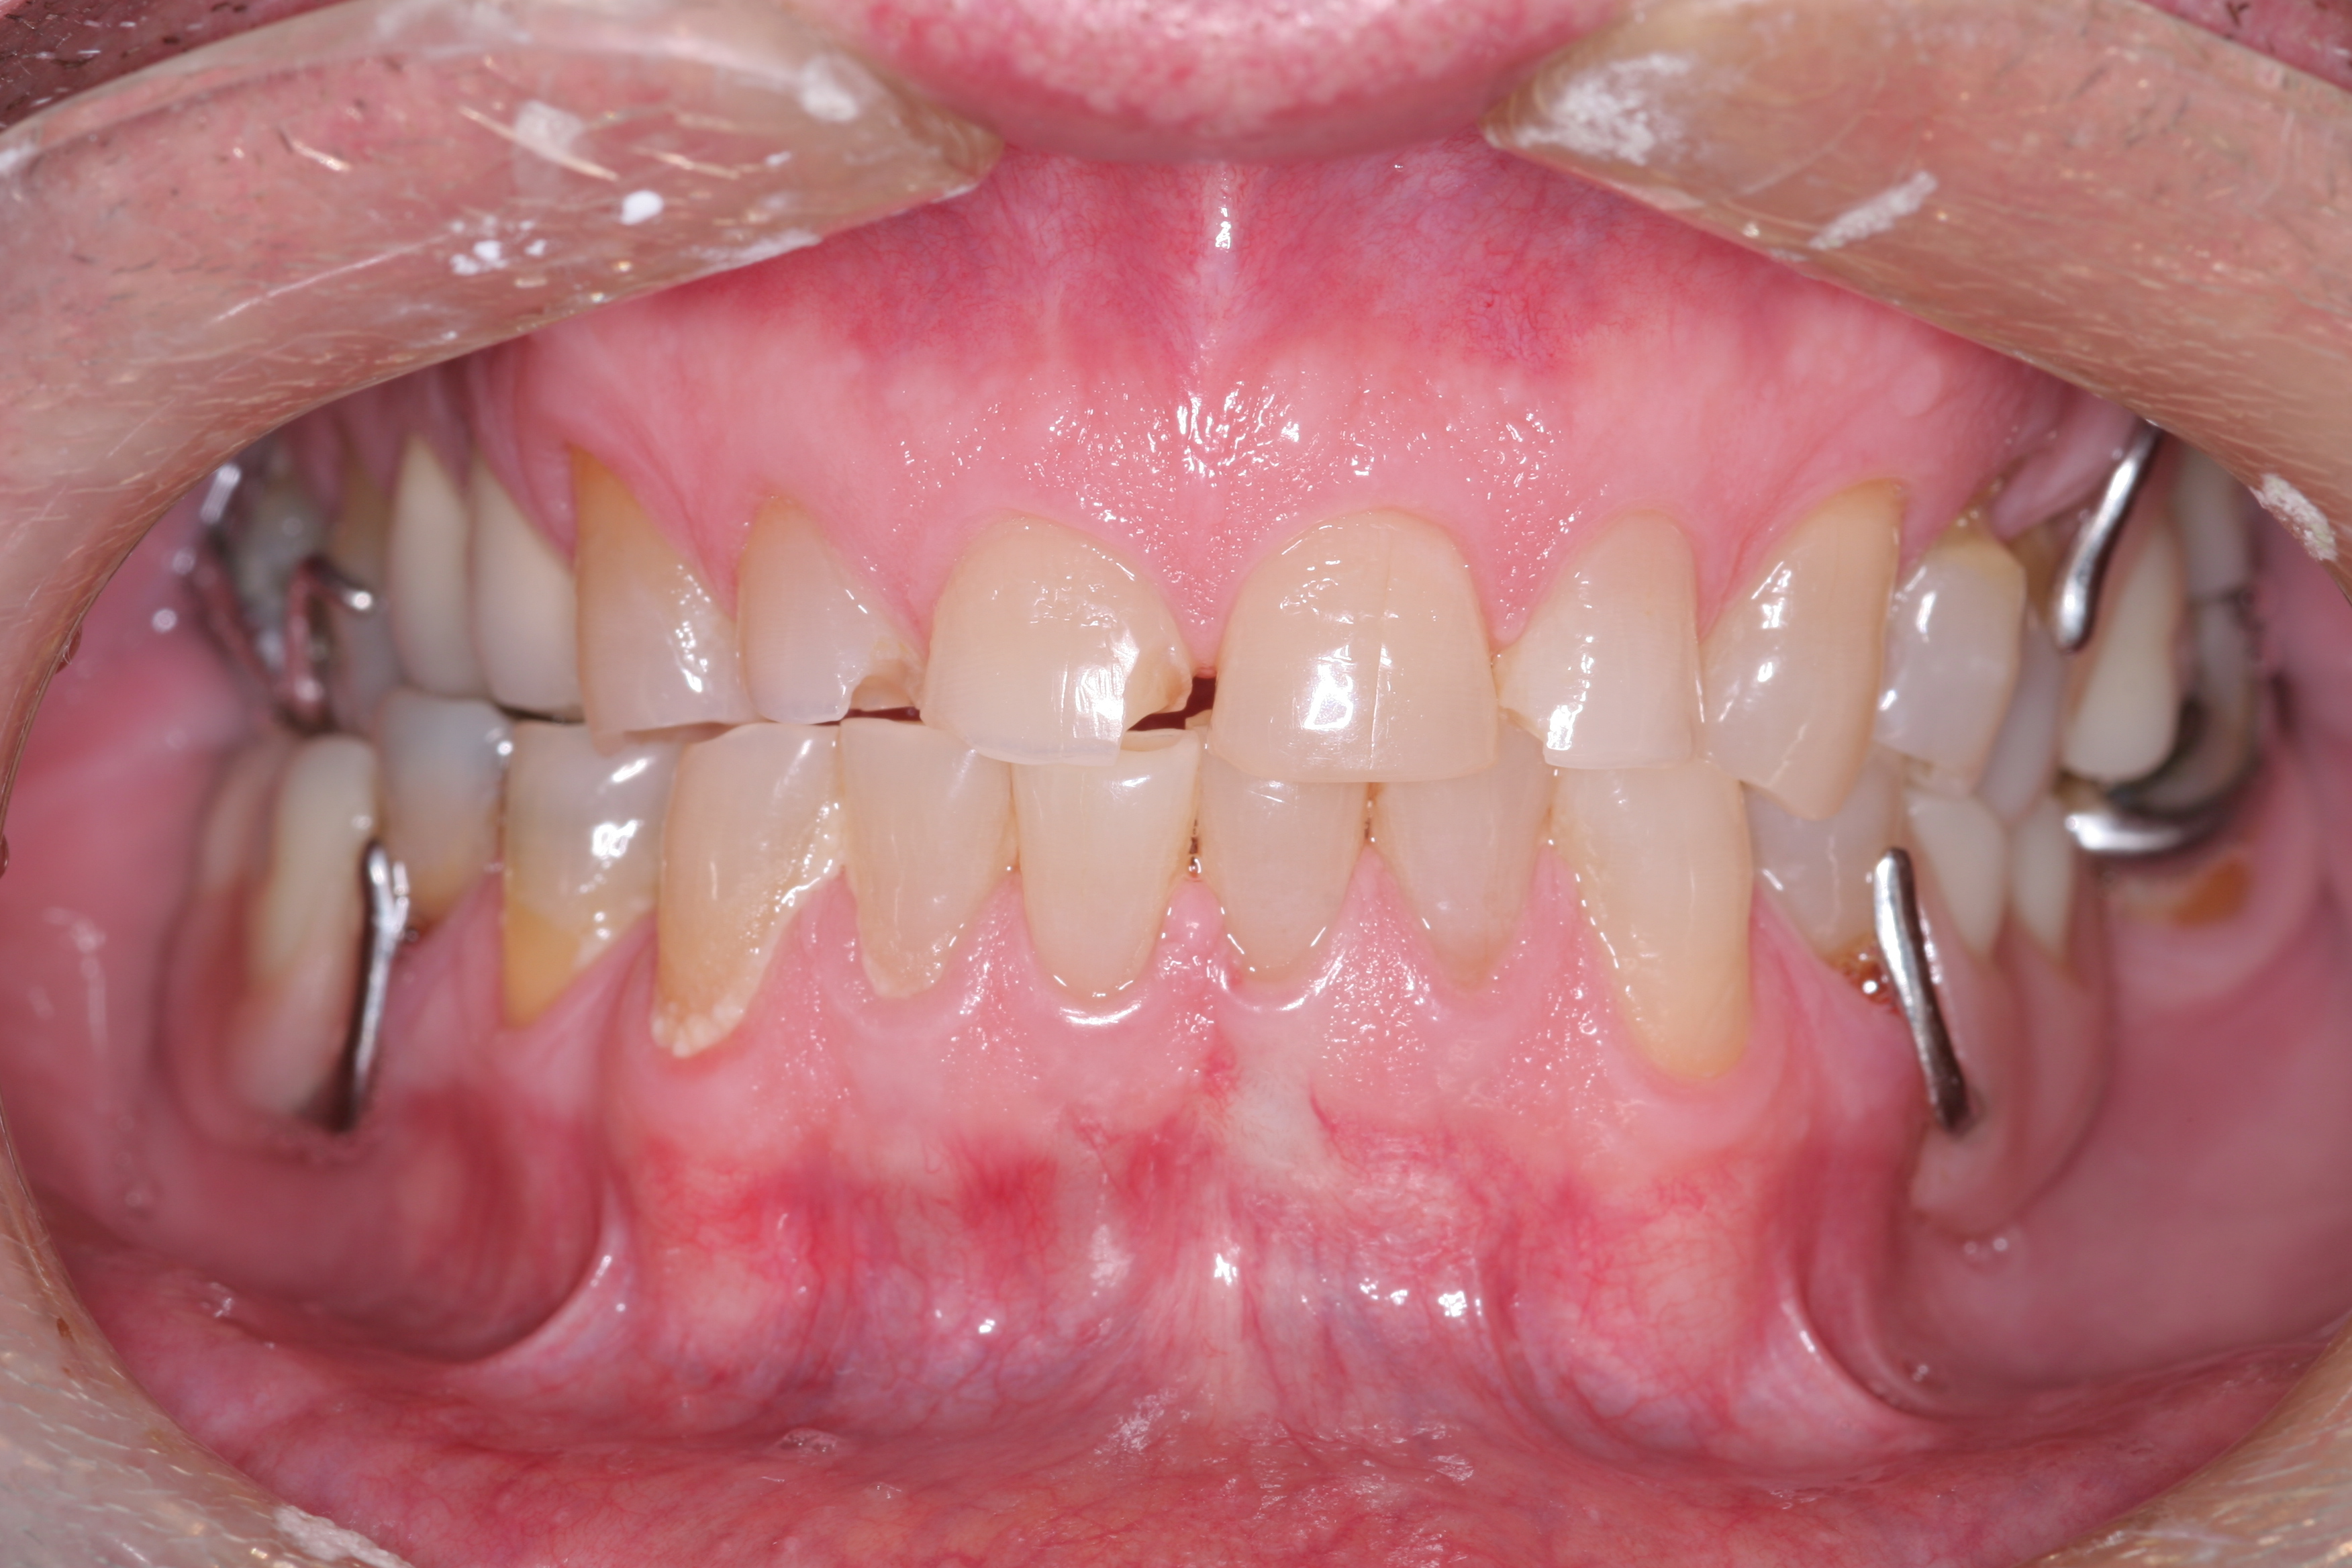

A patient presented with advanced generalized wear of her anterior teeth (Figure 10 and Figure 11). She was displeased with their overall appearance because of their color and wear (Figure 12). A complete examination was performed, revealing instability in her temporomandibular lateral poles bilaterally, sore muscles of mastication, advanced wear, a CR/MIP discrepancy, and loss of her anterior guidance due to the wear. Although the topic is beyond the scope of this article, the patient was also screened for possible sleep apnea. This included an evaluation of the Mallampati score, previous sleep therapy evaluation or treatment, snoring history, an evaluation of her neck size, her weight status, and the presence of the tonsils and their size. In every case, if this clinician suspects airway obstruction to be playing a role in tooth wear issues, the patient is referred to a sleep physician. The patient in this case displayed few apnea risk factors, and the patient’s anterior wear facets fit together like a “lock and key” pattern seen in parafunctional activity. Splint therapy was initiated to stabilize the joints and muscles. A repeatable CR position was verified through load testing. At this point diagnostic models, photographs, a CR bite record, and a facebow were taken and recorded.

(11.) A patient presented with advanced generalized wear of her anterior teeth, and was displeased with their overall appearance because of their color and wear.

Figure 11

(12.) A patient presented with advanced generalized wear of her anterior teeth, and was displeased with their overall appearance because of their color and wear.

Figure 12